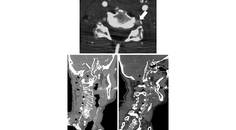

Ischemic Complications from a Facial Lipofilling Procedure